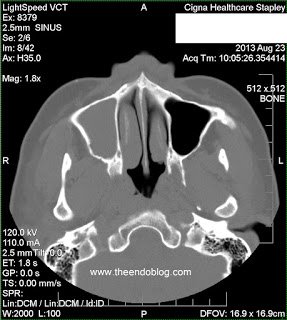

This patient presented to Arizona Sinus Center for evaluation of chronic sinus issues. She presented with chronic, unilateral nasal and facial symptoms, along with foul smelling nasal discharge. Nasal endoscopy was performed and findings include:

- RADIOGRAPHIC FINDINGS:

Endodontic diagnosis, including CBCT, determines that tooth #2 has a prior root canal with a root fracture and extraction is recommended. Tooth #3 has a prior RCT with apical abscess – caused by a missed MB#2 canal during the initial root canal treatment. Retreatment of the root canal #3 is recommended.

After 6 months, extraction of tooth #2 and retreatment of tooth #3 has shown periapical healing. The potential odontogenic source of the sinus infection has been eliminated. Since the Mx sinus continues to show opacification, the patient is referred back to Dr. Haegen for continued sinus evaluation and treatment.